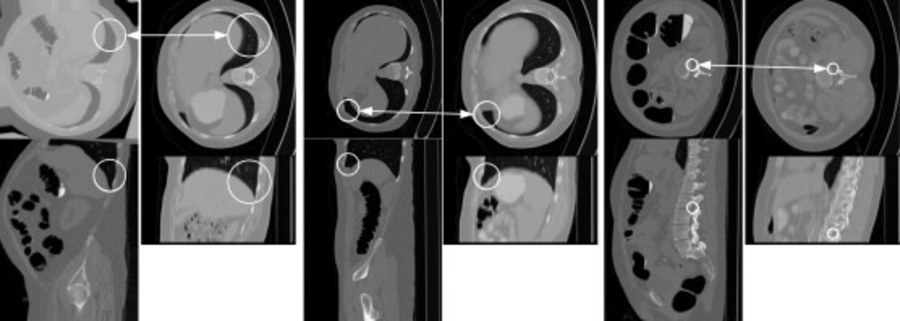

Feature-based analysis (FBA) is a recent technique in which data are represented as a set of distinctive local features or patches rather than the more traditional image voxels. Here, we show feature-based alignment (FBA), a general method for efficient and robust model-to-image alignment. Volumetric images, e.g., CT scans of the human body, are modeled probabilistically as a collage of 3D scale-invariant image features within a normalized reference space. The example shows model-subject correspondences in CT volumes. Each image consists of upper (axial) and lower (sagittal) image slices. White circles illustrating the location and scale of features in the ACRIN model (left) and in the new subject (right). The arrows indicate corresponding features [Toews, 2012].